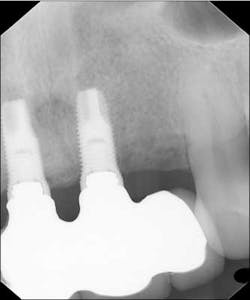

Fig. 2